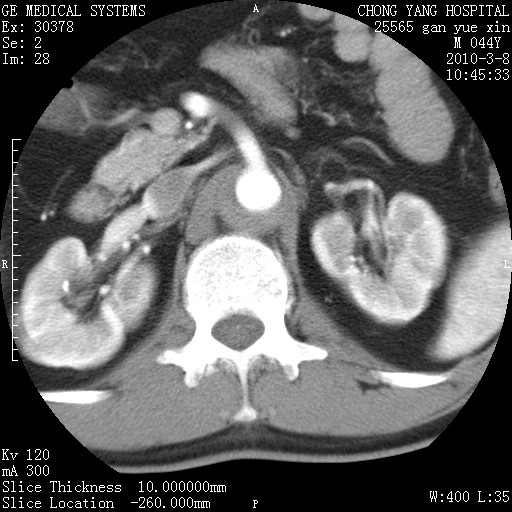

标题: CT24940:主动脉增强,典型病例。 [打印本页]

标题: CT24940:主动脉增强,典型病例。

夹层动脉瘤。

动脉夹层

夹层动脉瘤,典型

主动脉夹层。

动脉夹层的分型:

⒈debakey分型:根据主动脉夹层累及部位,分为三型:ⅰ型:原发破口位于升主动脉或主动脉弓部,夹层累及升主动脉、主动脉弓部、胸主动脉、腹主动脉大部或全部,少数可累及髂动脉。ⅱ型:原发破口位于升主动脉,夹层累及升主动脉,少数可累及部分主动脉弓。ⅲ型:原发破口位于左锁骨下动脉开口远端,根据夹层累及范围又分为ⅲa,ⅲb。ⅲa型:夹层累及胸主动脉。ⅲb型:夹层累及升主动脉、腹主动脉大部或全部。少数可累及髂动脉。

⒉stanford分型:a型:夹层累及升主动脉,无论远端范围如何。b型:夹层累及左锁骨下动脉开口以远的降主动脉。

夹层动脉瘤,少量胸水

夹层动脉瘤;左侧少量胸腔积液。

典型主动脉夹层。